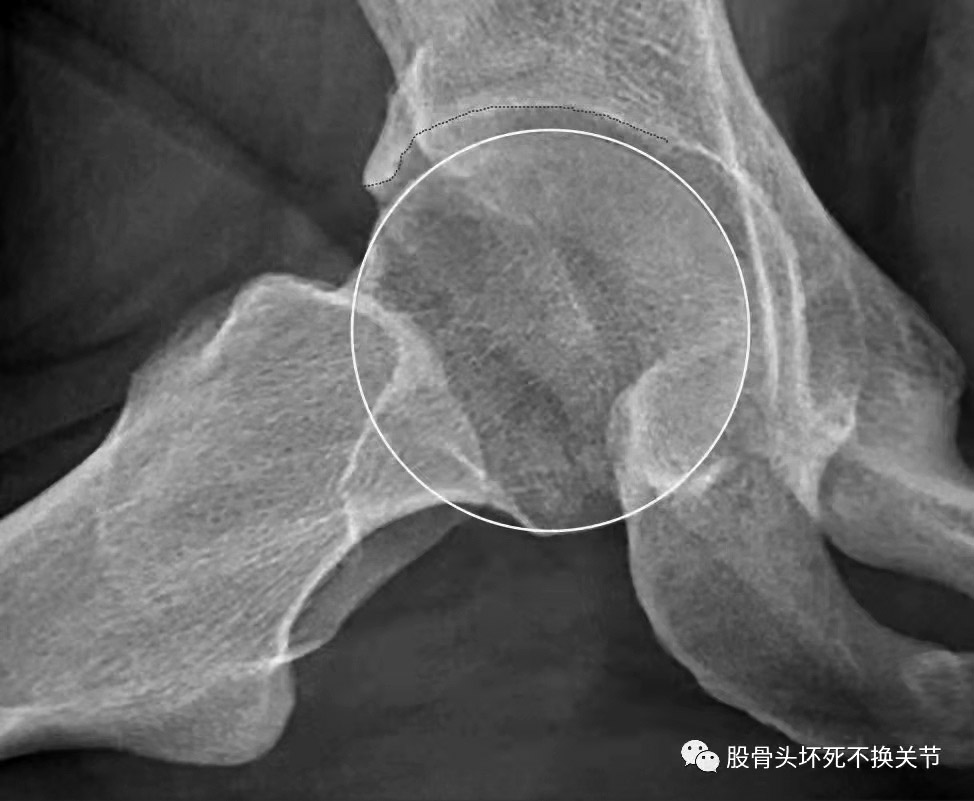

在治疗髋关节疼痛类疾病时,患者往往担心股骨头的血运问题。人体是一个大整体,髋关节是其中的一部分,股骨头和髋臼任何一方出了问题都会“报警”——疼痛或功能受限。 股骨头髋臼撞击综合征(FAI)是髋关节疼痛的常见原因之一,是股骨头颈部与髋臼边缘机械碰撞,导致相邻和对侧髋臼软骨发生损伤,被认为是导致髋关节骨性关节炎(OA)的主要原因。 FAI主要分为凸轮型和钳夹型,以及二者的混合型(约86%的患者为混合型)。 在凸轮型FAI中,股骨头颈交界处的骨性畸形在髋关节屈曲时进入髋关节,反复撞击髋臼盂唇,引起盂唇撕裂损伤,并造成髋臼周围软骨撕脱,即所谓的“地毯现象”。 在钳夹型FAI中,由髋臼内陷、髋臼后倾等导致的髋臼过度包容,使股骨头颈紧靠髋臼边缘,造成一个非常大的股骨头偏心距畸形,或引起股骨颈相对变宽、变短。一般来说,撞击部位位于髋臼前外侧,造成撞击部位盂唇硬化,但是局部损伤较小,对侧软骨损伤要比盂唇损伤的发生时间靠后。 FAI的发生和髋关节的形状密切相关,并且似乎具有高度遗传性,同时主要与生物力学存在密切关系。一般认为FAI和OA的发展之间的力学关系是这样的:凸轮型FAI继发OA被认为是由髋臼边缘盂唇和软骨,或者两者任何一方因撞击反复发生损伤造成的;而在钳夹型FAI中,股骨头前上部覆盖增加造成髋臼反复摩擦,从而发生损伤。回顾性研究和前瞻性研究均表明,FAI患者多并发OA,反之亦然。 症状轻微的患者口服非甾体抗炎药、休息即能改善;关节内注射玻璃酸钠或PRP(自体全血经离心后自体血小板的浓集物)能快速缓解疼痛,但彻底止痛、改善功能还要依靠外科手术。在这方面,开放性手术(就是传统的开刀手术,需要切开患者的皮肤以及皮下组织)和关节镜手术都能达到较好的疗效。从直观上讲,就是外科手术能够消除撞击,减少软组织结构的继发性损伤,避免髋关节进一步退变,从而阻止OA的发生。 下面介绍一个典型病例。 一名中年女性患者,无明确诱因出现双侧大腿内侧疼痛、下蹲受限。患者自述10年前有骨盆骨折病史,担心发生股骨头坏死,来到河南省洛阳正骨医院就诊。 我们看一下患者的X线片。 图1中箭头1和箭头2提示,双侧髋臼边缘包容过度,造成患者疼痛和活动受限。 放大之后看得更加清楚(图2)。 可以看到,患者的右侧股骨头外缘关节间隙狭窄,股骨头与髋臼的间隙不均匀,其“骨刺”其实就是不断损伤、钙化的盂唇。 综上所述,对患者进行特殊部位X线检查、CT检查、MRI(磁共振)检查,可进一步了解股骨头与髋臼的匹配关系、盂唇损伤钙化和股骨头骨髓水肿的情况,为下一步手术治疗提供依据。 (作者供职于河南省洛阳正骨医院)